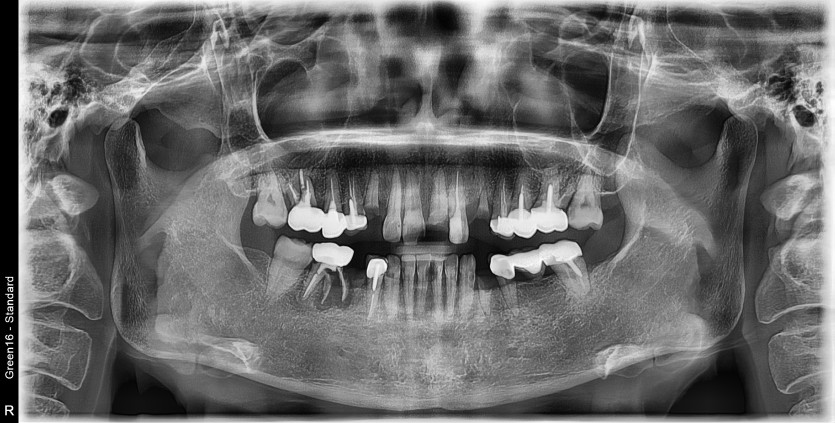

만 56세 전체 임플란트 증례

전체 임플란트 증례입니다.

17개의 임플란트로 완성하였습니다.